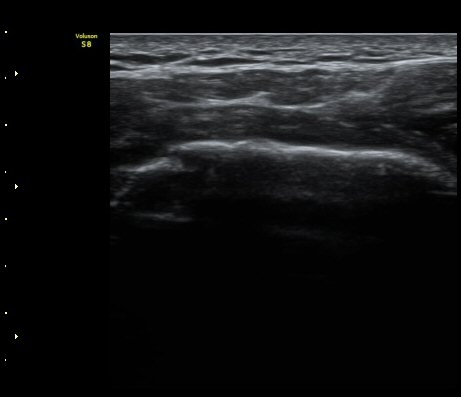

°ß°©ÇÏ±Ù°Ç Á¾´Ü¸é°Ë»ç¿Í Ⱦ´Ü¸é°Ë»ç¿¡¼­ °ß°©ÇϱٰÇÀÇ ÀüÃþÆÄ¿­ ¼Ò°ßÀ» º¸ÀÓ(»çÁø 5, 6)